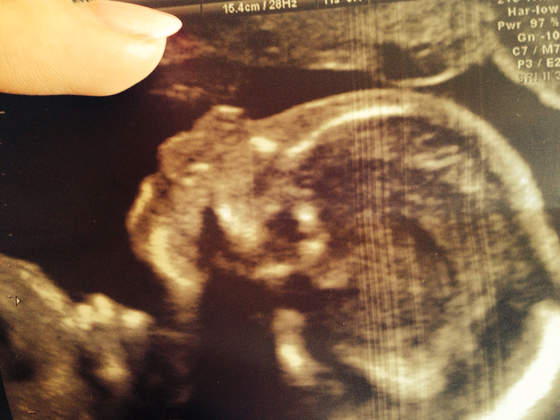

A tu nasza buzka i klejnociki pięknie widoczne